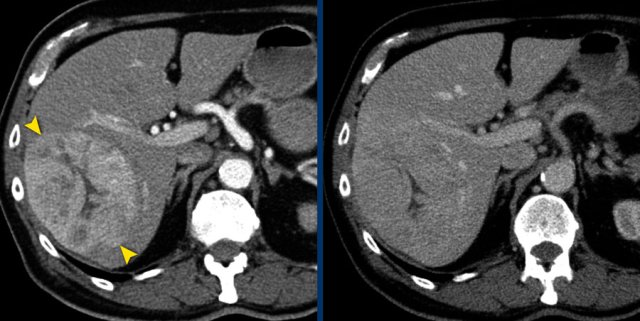

Mesothelioma

An exception to measuring the longest diameter is in patients with malignant pleural mesothelioma.

The non-spherical growth pattern in this disease makes reproducible long axis measurements difficult.

Therefore not the longest diameter, but the tumour thickness perpendicular to the chest wall is used.

This measurement has a good correlation with outcome.

CT images in a 63-year-old male with malignant pleural mesothelioma.

Measurements according to the modified RECIST 1.1 for malignant pleural mesothelioma with measurement of the tumour thickness perpendicular to the chest wall or mediastinum in two positions at three different levels, preferably in the upper thorax.